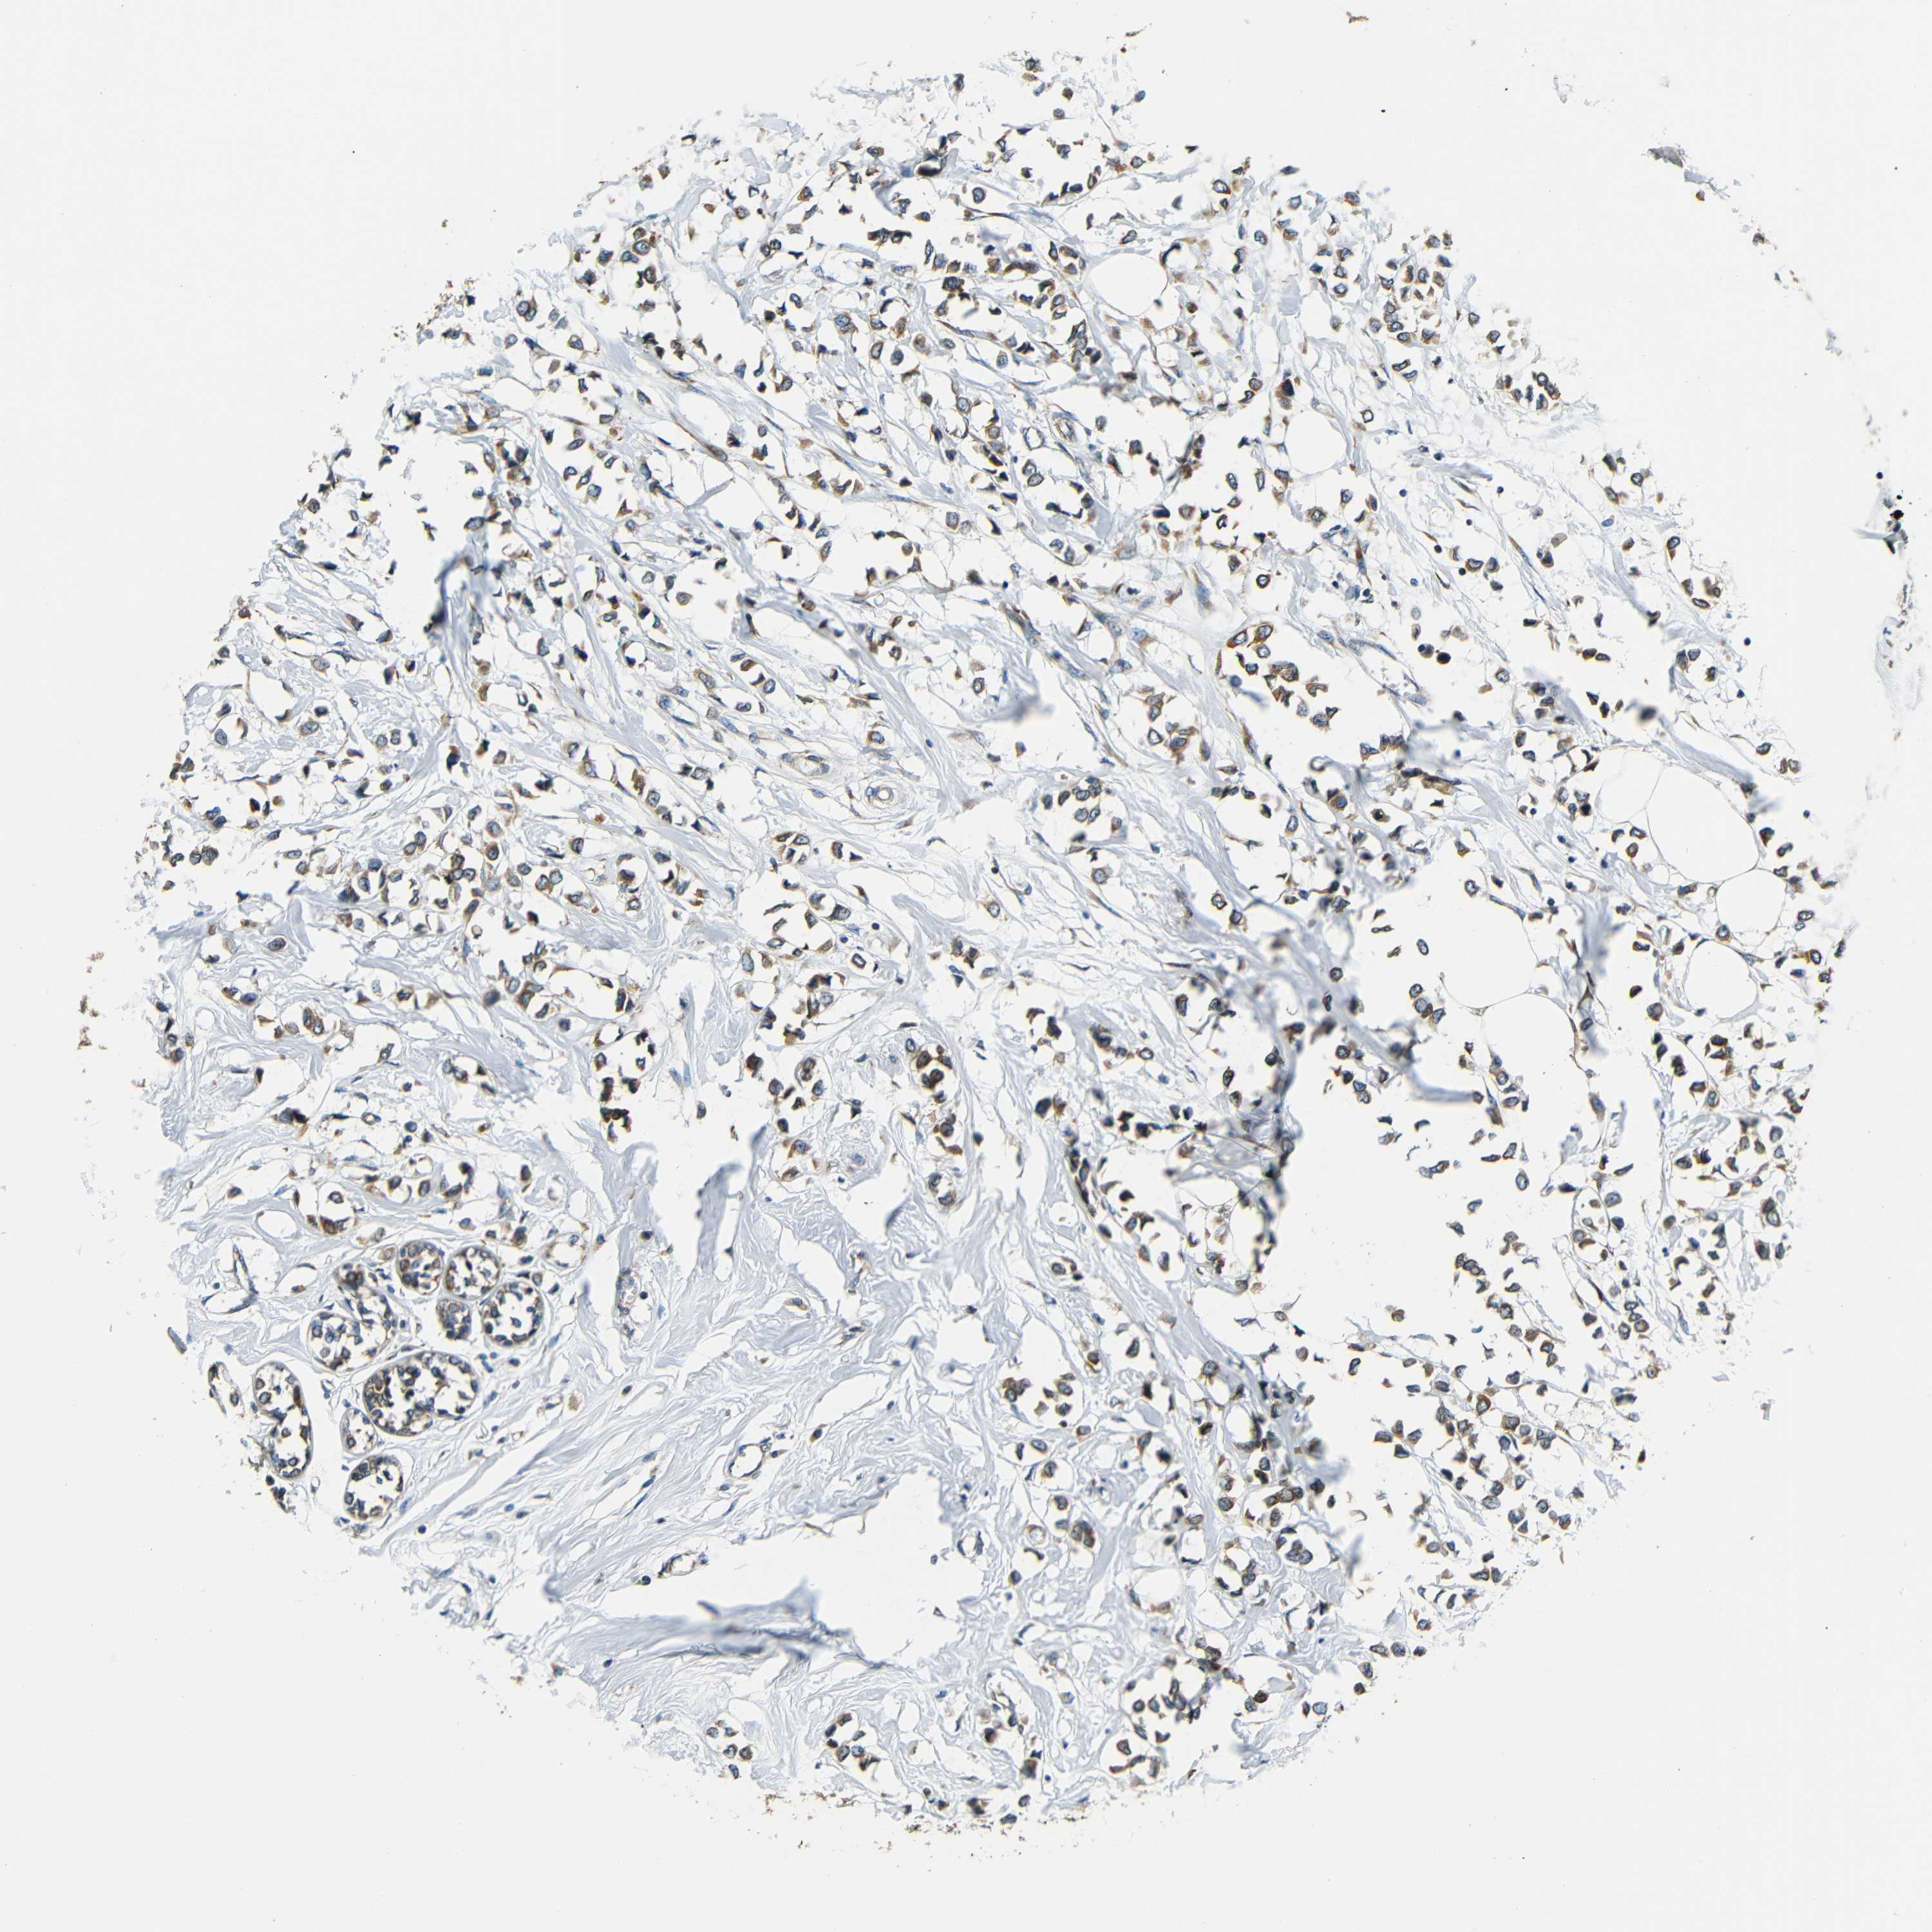

BRCA TCGA BRCA VALIDATION PROTEIN EXPRESSION